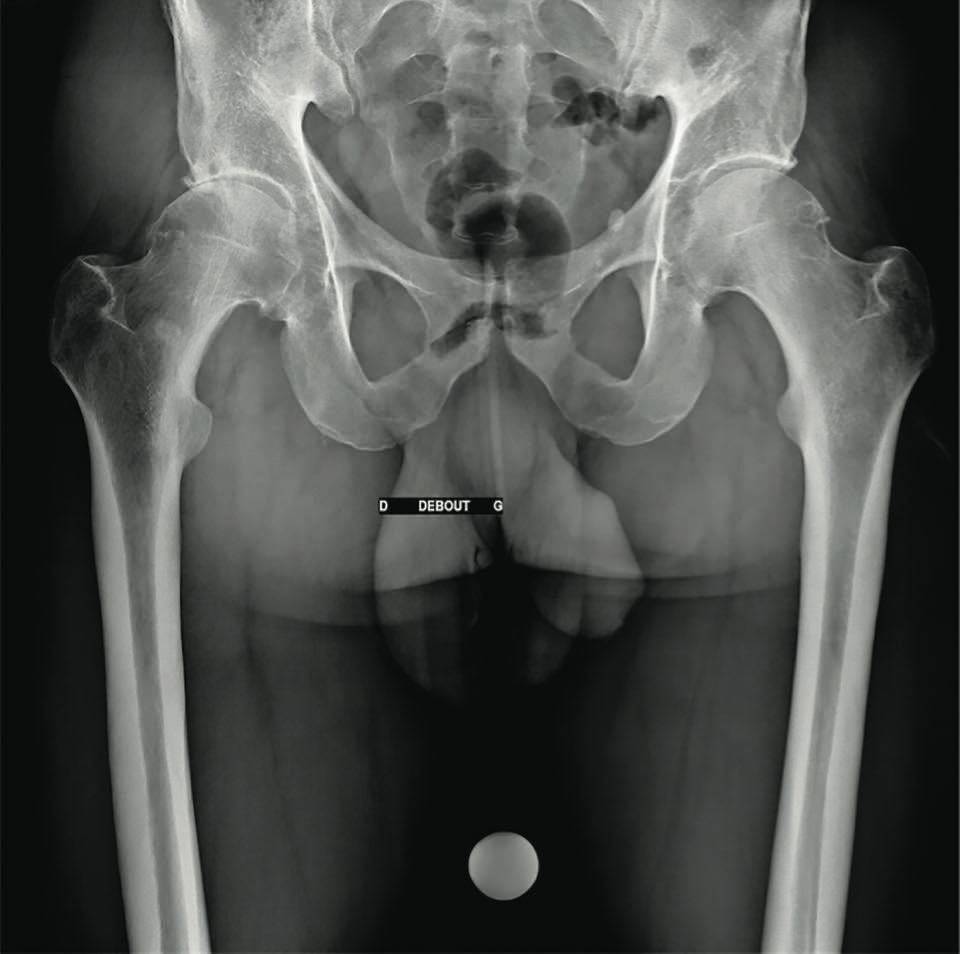

Technologie Analyse de la fiabilité du logiciel Traumacad et de l’influence du chirurgien dans la programmation des prothèses totales de hanche , Frédéric Sailhan Clinique Arago, Paris, France , L. Jacob Hôpital Cochin, 27 rue du Faubourg Saint-Jacques, Paris, France , B. Hachache Institut de Chirurgie de la Hanche et du Genou, Espace Médical Vauban, 2a Avenue de Ségur, Paris, France , Jean-Marie Postel Institut de Chirurgie de la Hanche et du Genou, Espace Médical Vauban, 2a Avenue de Ségur, Paris, France , Philippe Lapresle Clinique Arago, 187 A Rue Raymond Losserand, 75014 Paris, France , Luc Kerboull Espace Médical Vauban, Paris, France N°260 - Janvier 2017 ● 14 min de lecture